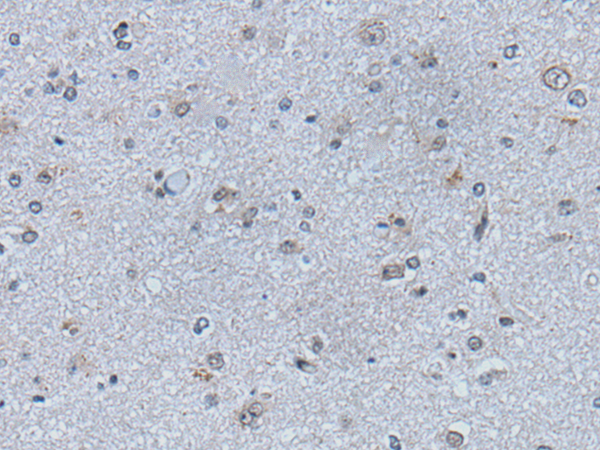

分类: 科研抗体货号: P05945别名: CFND; CFNS; EFB1; EFL3; EPLG2; Elk-L; LERK2应用: IHC反应种属: Human, Mouse, Rat